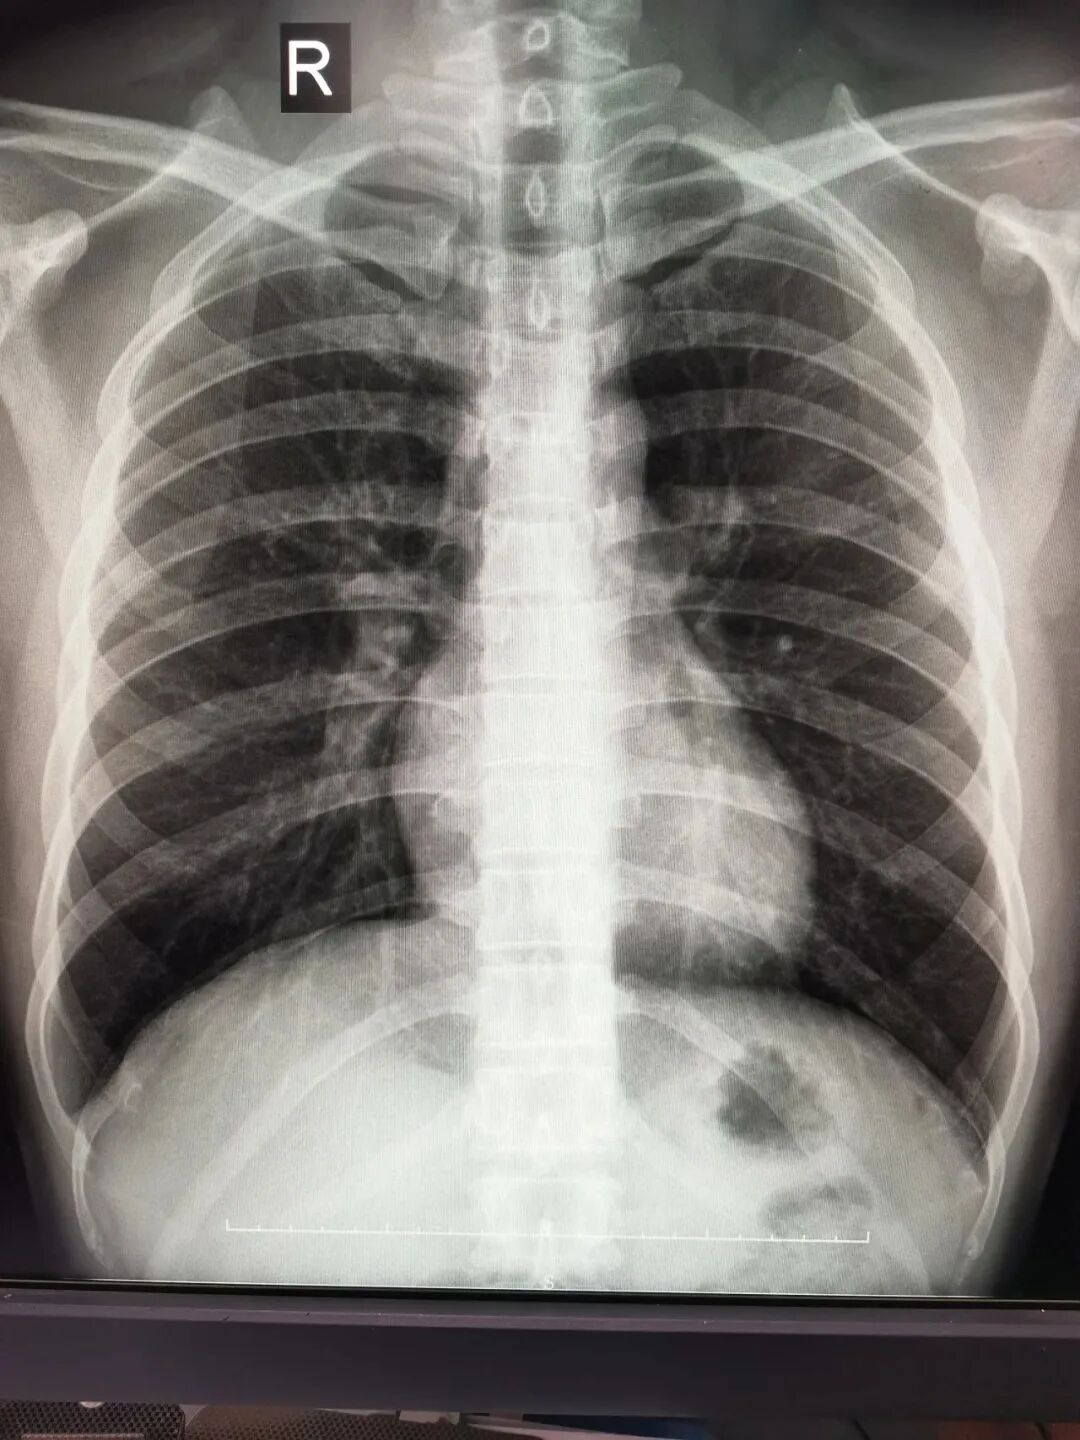

X光 像把面包压扁了看

X光能穿过人体,因为X线对不同部位以及骨骼、肌肉等不同组织的穿透力不一样,所以能在特制的胶片上生成影像。

就像一片面包或一块棉花,看不到里面的纤维纹理,但用手压瘪了会清晰一些。X光最大缺点是受制于深浅组织的影像相互重叠和隐藏,有时需要多次多角度拍摄X光片。

3、胸部——粗看X光片,细看CT。

X光胸片可粗略检查心脏、主动脉、肺、胸膜、肋骨等,可以检查有无肺纹理增多、肺部钙化点、主动脉结钙化等。

胸部CT检查显示出的结构更清晰,对胸部病变检出敏感性和显示病变的准确性均优于常规X光胸片,特别是对于早期肺癌筛查有决定性意义。但是CT检查的辐射剂量高于X光。核磁共振对于肺部疾病的诊断,应用非常有限。